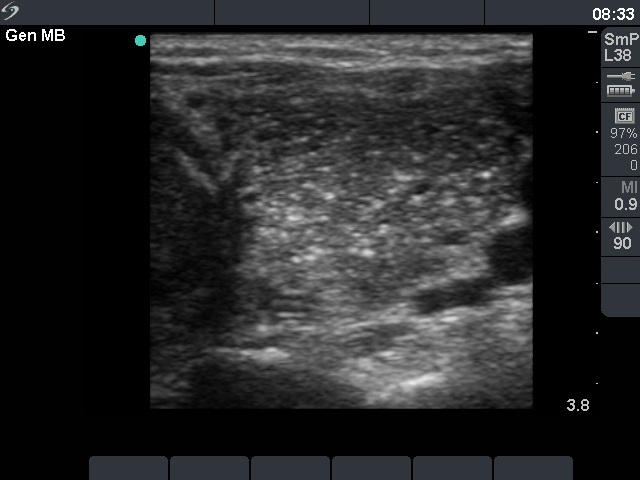

Lymph nodes - case conp 011 (ultrasonographic picture 4)

Left lobe, transverse scan. This lobe is significantly more inmohogeneous because of the presence of numerous hyperechogenic granules.